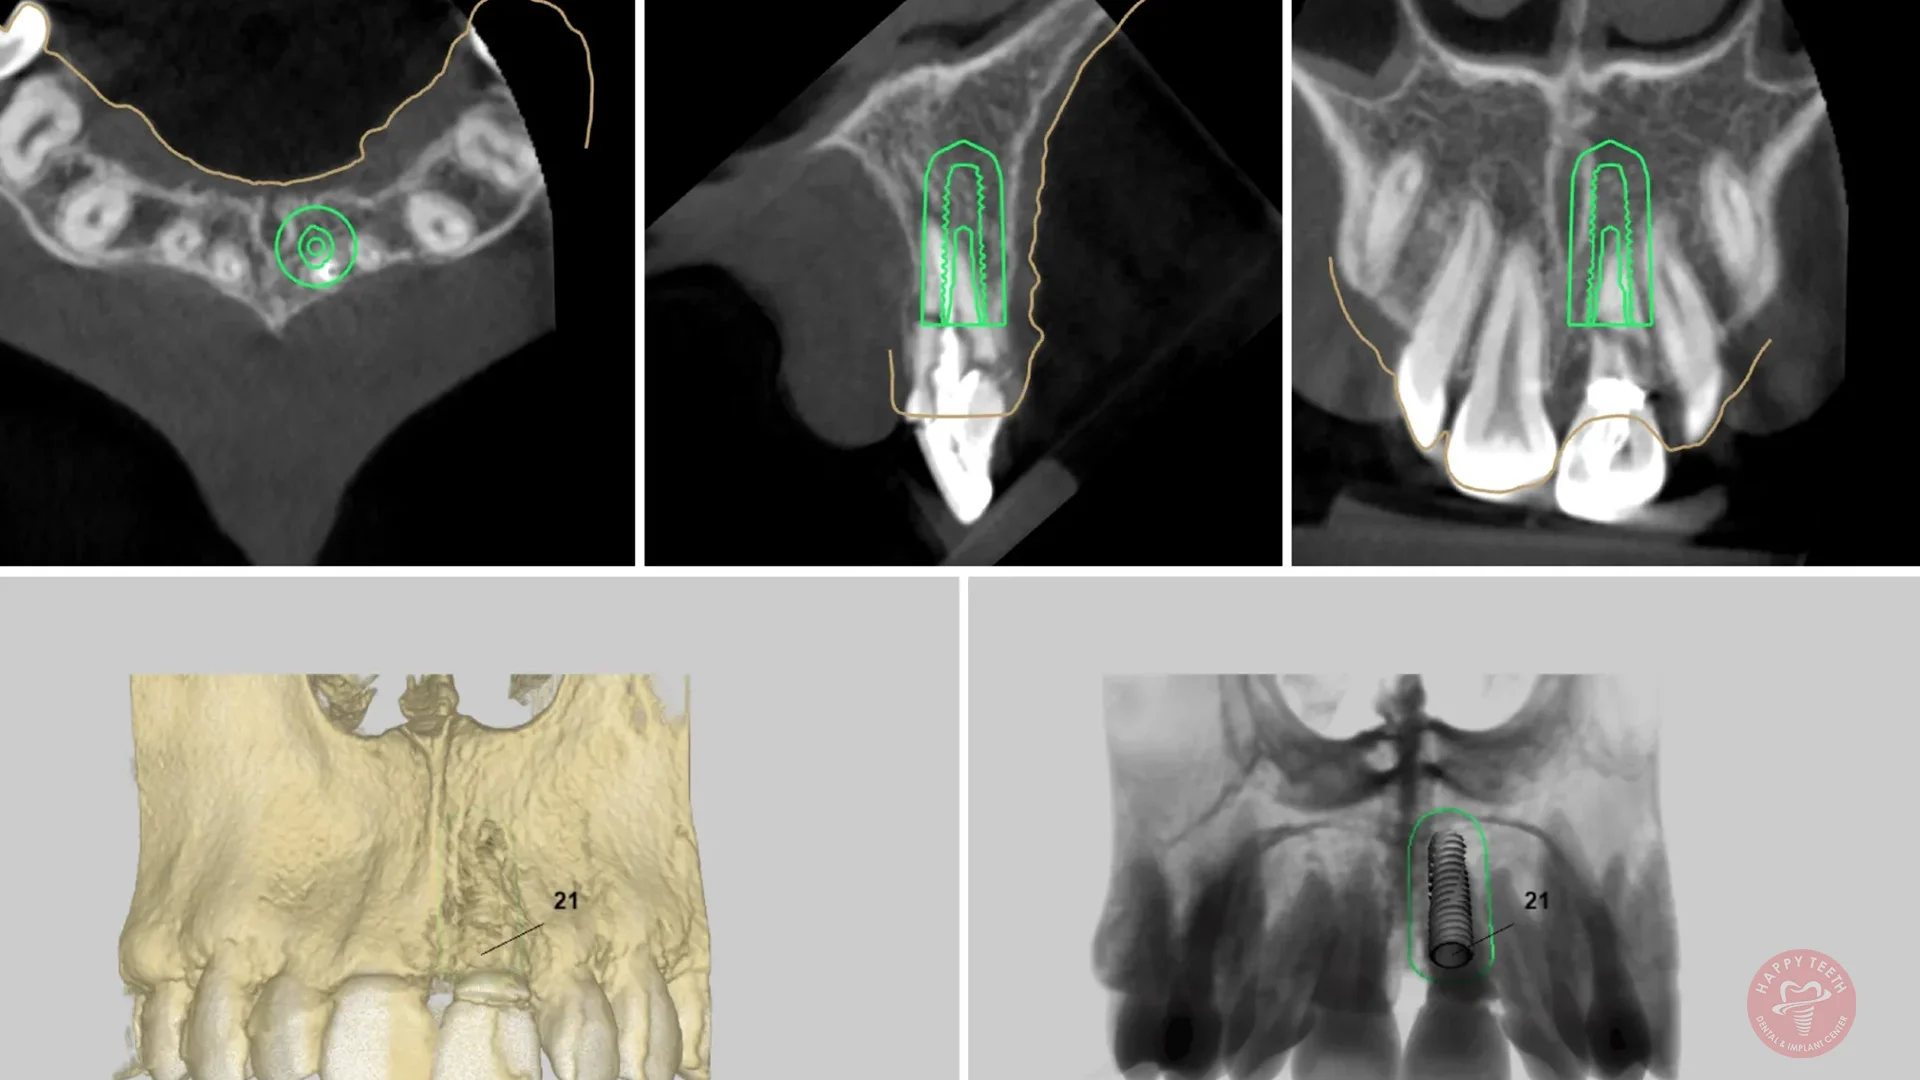

Considering dental implants? This guide covers everything from the implant process and benefits to aftercare tips, helping you make an informed decision about your dental health.